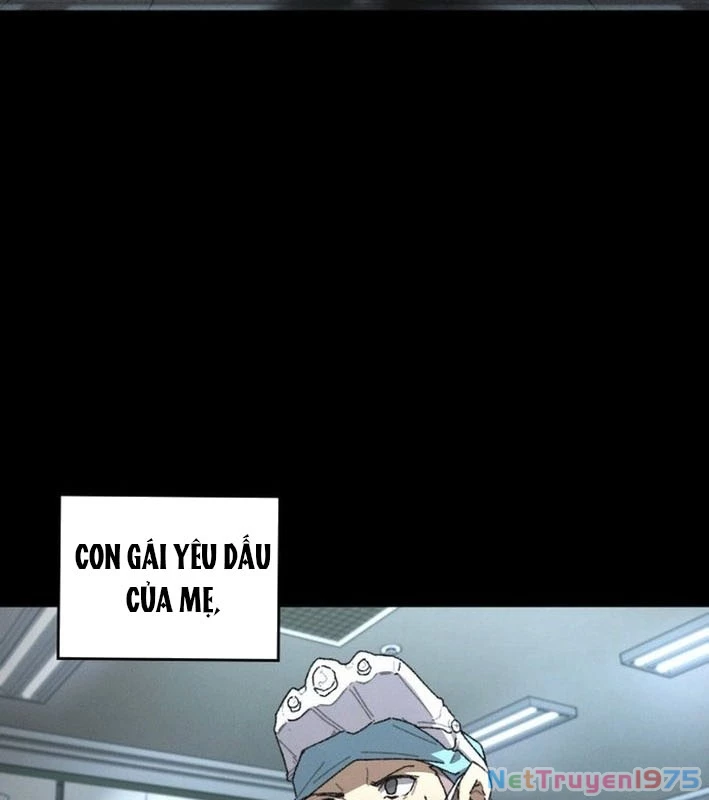

Kẻ Chôn Cất Quái Vật - Chapter 1